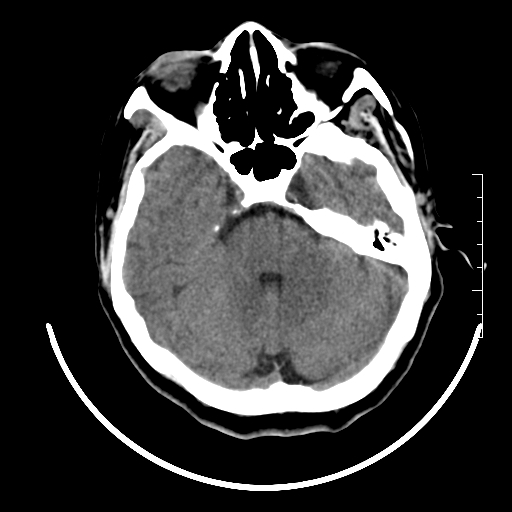

标题: CT27880:f、55y,头痛。 [打印本页]

标题: CT27880:f、55y,头痛。

考虑左侧顶部镰旁脑膜瘤;建议行ct增强扫描检查。

考虑左侧顶部镰旁脑膜瘤,建议行ct增强扫描检查。

考虑左侧顶部镰旁脑膜瘤;建议行ct增强扫描检查

大脑镰旁脑膜瘤可能,建议增强或mri

左侧顶部镰旁脑膜瘤,增强